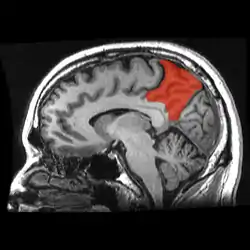

| Precuneus | |

![]() Sagittal MRI slice with the precuneus shown in red. (Anterior to the left.) | |

In neuroanatomy, the precuneus is the portion of the superior parietal lobule on the medial surface of each brain hemisphere. It is located in front of the cuneus (the upper portion of the occipital lobe). The precuneus is bounded in front by the marginal branch of the cingulate sulcus, at the rear by the parieto-occipital sulcus, and underneath by the subparietal sulcus. It is involved with episodic memory, visuospatial processing, reflections upon self, and aspects of consciousness.

The precuneus is located on the inside between the two cerebral hemispheres in the rear region between the somatosensory cortex and forward of the cuneus (which contains the visual cortex). It is above the posterior cingulate. Following Korbinian Brodmann it has traditionally been considered a homogeneous structure and with limited distinction between it and the neighboring posterior cingulate area. Brodmann mapped it as the medial continuation of lateral parietal area 7.